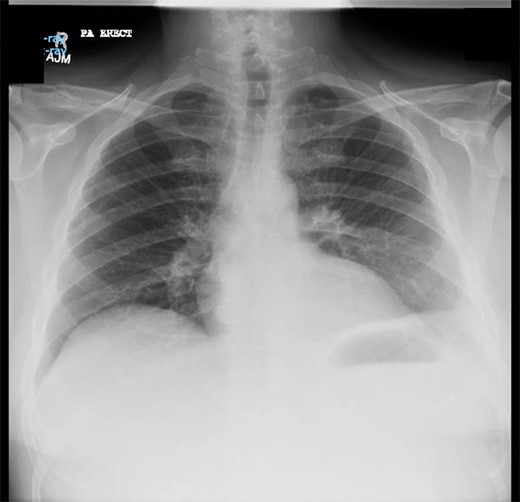

Chest X-ray in ICU following drainage showed what was thought to be Pneumomediastinum (Figs 1 and 2), and given this concern he was referred to the Cardiothoracic service. Subsequent CT suggested a large loculated hydro-pneumothorax, which in retrospect represented the drained Pseudocyst communicating through the diaphragm (Figs 3 and 4).

Chest X-ray prior to transgastric drainage. Suggestive of Left pleural effusion/ lower lobe collapse.